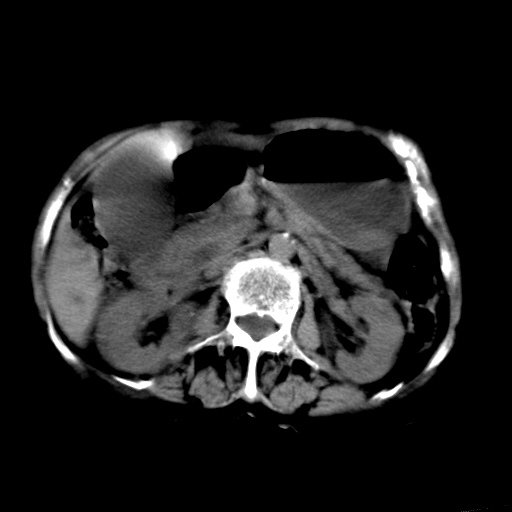

以下是引用杀毒软件在2009-3-4 17:38:00的发言:[br]为何没有喝照影剂呀? 胆总管及肝内胆管扩张,增强吧。[br][br]考虑-----十二指肠占位----建议----十二指肠镜检查[br][br]

以下是引用jiangjing在2009-3-4 17:45:00的发言:[br]低位胆道梗阻。十二指肠降段局部管壁增厚。扫描效果不理想,建议ct增强及ercp。

以下是引用杀毒软件在2009-3-4 17:38:00的发言:[br]为何没有喝照影剂呀? 胆总管及肝内胆管扩张,。增强吧。[br][br]考虑-----十二指肠占位----建议----十二指肠镜检查[br][br][br][br][本贴已被 杀毒软件 于 2009-3-4 17:56:38 修改过]